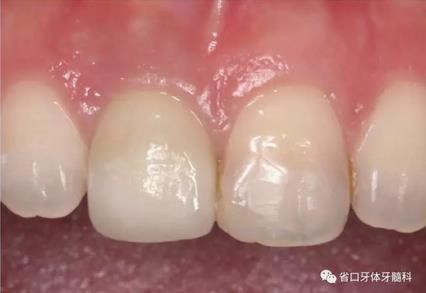

圖33 就位全瓷冠

圖34 負(fù)重3個(gè)月后

圖35 負(fù)重6個(gè)月后復(fù)診

(4)最終修復(fù)與隨訪:經(jīng)過(guò)3個(gè)月左右的塑形,上頜右側(cè)中切牙臨時(shí)修復(fù)固位良好,菌斑控制良好,近遠(yuǎn)中齦乳頭充盈良好,齦緣水平及形態(tài)與 鄰牙相對(duì)稱。牙齦塑形穩(wěn)定后,以臨時(shí)修復(fù)體制作個(gè)性化轉(zhuǎn)移桿并取模轉(zhuǎn)移,并以原廠氧化鋯基臺(tái)制備個(gè)性化基臺(tái)及全瓷冠。正確就位最終基臺(tái),加 力30N·cm。制備粘接代型,去除多余粘接劑,以Unicem粘接固位上頜右側(cè)中切牙全瓷修復(fù)體。固化穩(wěn)定后,再次確定咬合無(wú)干擾。最終修復(fù)完成后 隨訪3個(gè)月及6個(gè)月,上頜右側(cè)中切牙種植修復(fù)固位穩(wěn)定,近遠(yuǎn)中齦乳頭充 盈良好,唇側(cè)齦緣水平穩(wěn)定。

上頜右側(cè)中切牙修復(fù)體固位良好,牙齦乳頭充盈良好,齦緣水平對(duì)稱 修復(fù)體與對(duì)側(cè)同名牙協(xié)調(diào)一致。外觀笑容美觀協(xié)調(diào)?;颊邼M意。X線檢查示 上頜右側(cè)中切牙種植體周穩(wěn)定骨質(zhì)包繞,唇側(cè)骨板>2mm,相鄰牙槽骨高度穩(wěn)定,基臺(tái)及修復(fù)體就位良好。分別根據(jù)Furhauser的PES和Bulser的WES 進(jìn)行美學(xué)評(píng)分,總分值為20,美學(xué)效果良好。